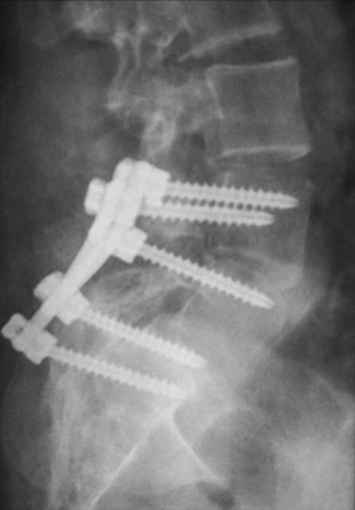

La espondilolistesis es cuando el defecto de la pars articularis es bilateral y se produce un desplazamiento o subluxación de la vértebra superior sobre la inferior. Es más común en la L5 sobre el sacro. La posibilidad del desplazamiento viene determinada por el potencial de crecimiento, por la presencia de cifosis lumbo-sacra y del grado de desplazamiento de una vértebra sobre la otra, al momento de la evaluación inicial. Es más frecuente el desplazamiento en pacientes mujeres jóvenes, cuando el desplazamiento inicial de una vértebra sobre la otra es mayor del 50%, cuando el tope del sacro es en forma de domo o cuando la unión lumbo-sacra es displásica. Se clasifica dependiendo de la etiología (congénita, ístmica, traumática, patológica e iatrogénica) o por el porcentaje de desplazamiento de una vértebra sobre la otra (clasificación de Meyerding). El historial mostrará un dolor de leve a moderado que se irradia a las piernas, se agrava con actividades y se alivia con el descanso. El examen físico observa una disminución de la lordosis lumbar, espasmos de los músculos isquíaticos con un caminar rígido. El diagnóstico se puede ver en radiografías lumbares laterales, pero las vistas oblicuas serán de gran ayuda en los casos más difíciles. En casos no evidentes puede ser de ayuda la cintigrafía ósea que mostrará hipercaptación en el área afectada (Figura 3). Además, la cintigrafía ósea permite saber el estadio de saneamiento. Si es agudo, habrá captación, si es crónico no habrá tanta captación. Al ser agudo, se espera mayor probabilidad de curación con tratamiento conservador y si es crónico la posibilidad de recuperación será muy pobre (34). La TC ayuda a delimitar el área más afectada. El tratamiento dependerá en el grado de desplazamiento y los síntomas. El tratamiento conservador consiste en modificar las actividades, medicación analgésica, una abrazadera y terapia física. La cirugía se indica cuando la terapia conservadora no mejora los síntomas, si hay alteraciones neurológicas o cuando el desplazamiento de una vértebra sobre otra es mayor del 50% (35). Quirúrgicamente se puede hacer una artrodesis in situ, sin instrumentación con una probabilidad de resolver el problema en un 70 % de los casos o una artrodesis instrumentada, con reducción o sin reducción del desplazamiento. La instrumentación permite corregir el defecto, aumenta la probabilidad de la fusión y mejora la mecánica espinal (Figura 4).